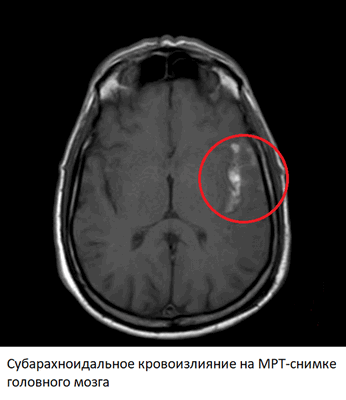

Субарахноидальные кровоизлияния

Субарахноидальные кровоизлияния - один из вариант геморрагического инсульта, однако источником кровотечения в этому случае служат разрывы аневризм артерий, расположенных на основании головного мозга. Гематома при субарахноидальном кровоизлиянии находится между мягкой и паутинной мозговой оболочкой. Предрасполагающим фактором также служит гипертоническая болезнь.

Изменения на МРТ после этого типа геморрагического инсульта видны сразу после начала болезни (в режимах SWI и FLAIR). Магнитно-резонансная томография легко обнаруживает кровь в субарахноидальном пространстве. В ангио-режиме можно увидеть непосредственную причину кровоизлияния - аневризму или другой источник кровотечения. В первые несколько дней на МРТ-снимках также могут обнаруживаться ишемические изменения, связанные с реактивным спазмом артерий головного мозга. Как и в случае с геморрагическими инсультами, субарахноидальное кровоизлияние уже через несколько часов видно в других режимах, из-за сворачивания крови.